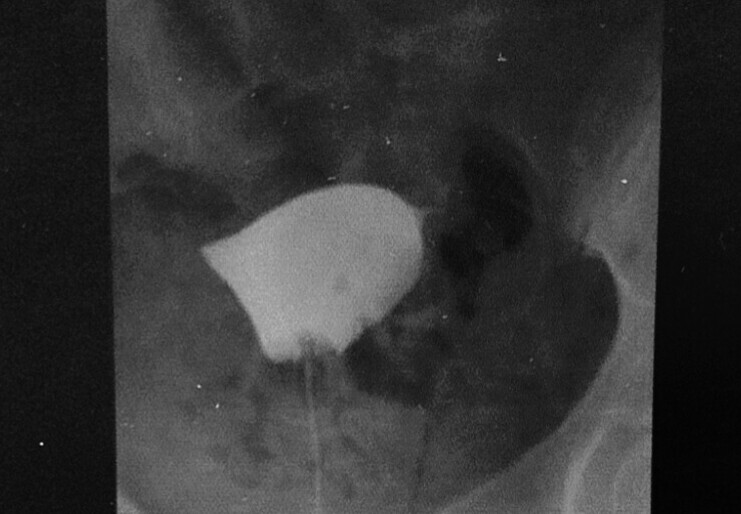

上記の方は、全く痛みを感じられず(通過のない場合はあまり痛みを感じることはありません)両側の卵管が閉塞(卵管は通っていない)している状態が確認されました。この方は正常な妊娠をすることは厳しいため、人工授精、体外受精など、不妊治療の次の段階をお勧めすることとなります。